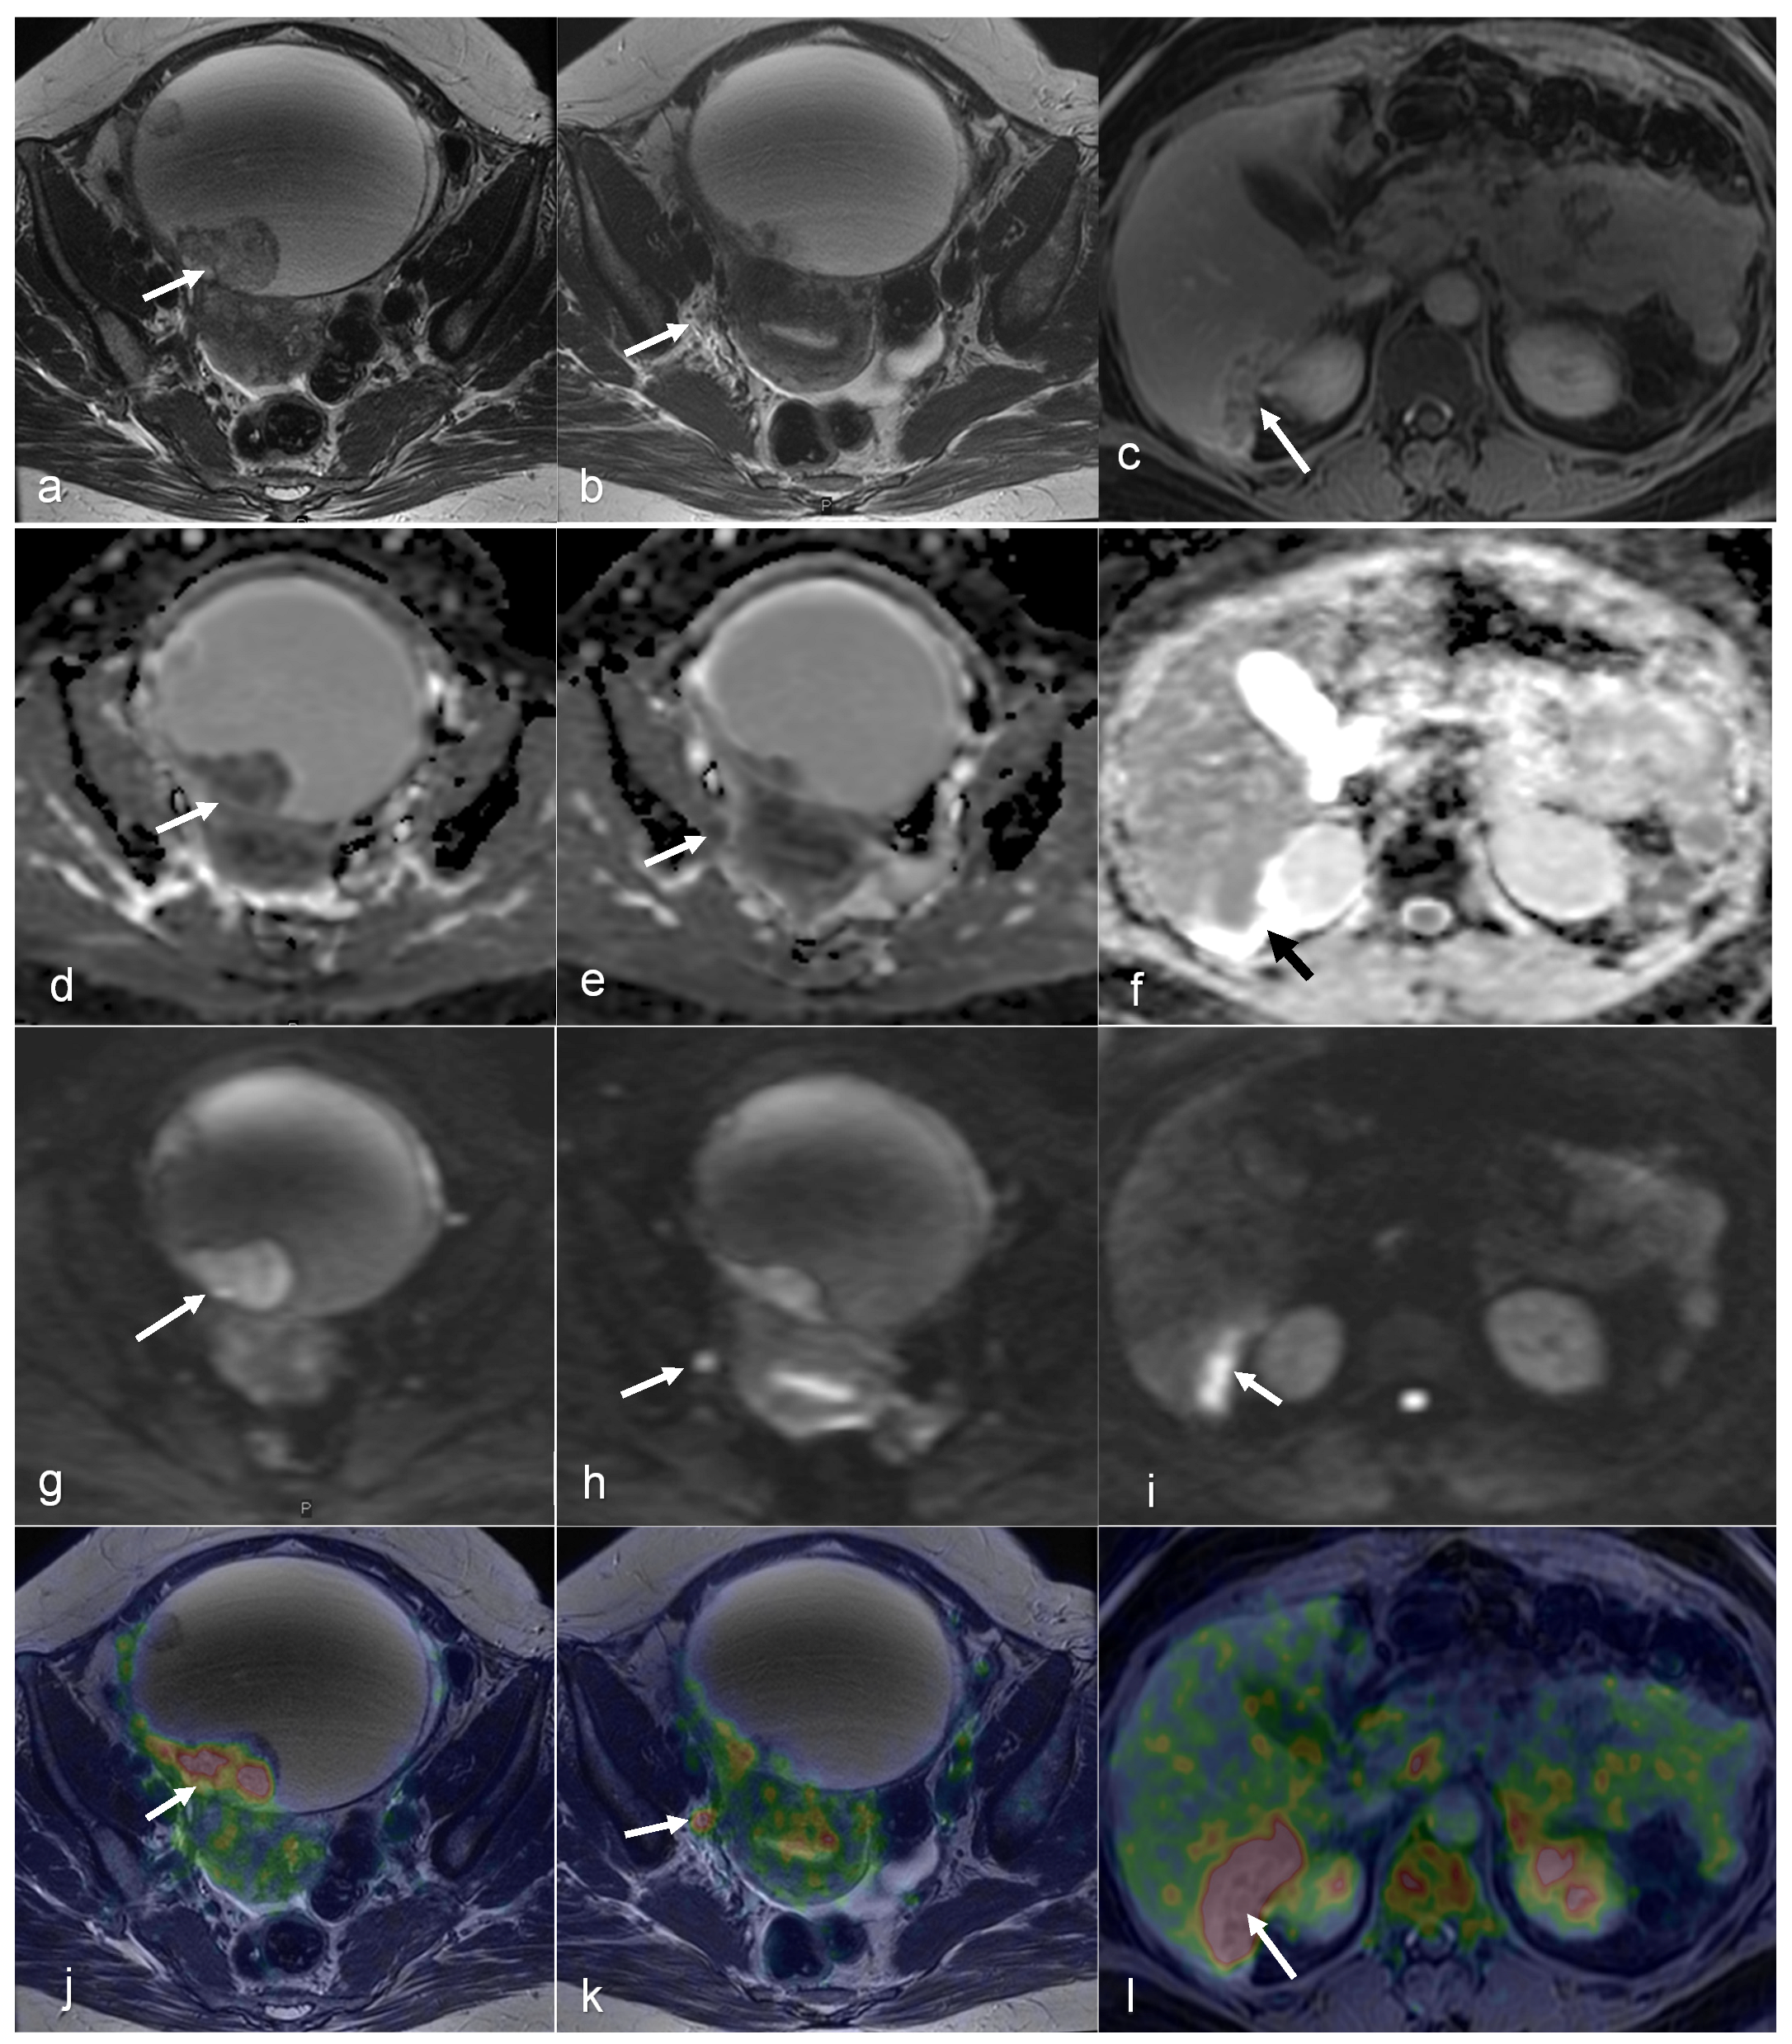

- Sadowski, E.A.; Lees, B.; McMillian, A.B.; Kusmirek, J.E.; Cho, S.Y.; Barroilhet, L.M. Distribution of prostate specific membrane antigen (PSMA) on PET-MRI in patients with and without ovarian cancer. Abdom. Radiol. 2023, 48, 3643–3652. [Google Scholar] [CrossRef]

- Xi, Y.; Sun, L.; Che, X.; Huang, X.; Liu, H.; Wang, Q.; Meng, H.; Miao, Y.; Qu, Q.; Hai, W.; et al. A comparative study of [(68)Ga]Ga-FAPI-04 PET/MR and [18F]FDG PET/CT in the diagnostic accuracy and resectability prediction of ovarian cancer. Eur. J. Nucl. Med. Mol. Imaging 2023, 50, 2885–2898. [Google Scholar] [CrossRef]

- Fiaschetti, V.; Calabria, F.; Crusco, S.; Meschini, A.; Nucera, F.; Schillaci, O.; Simonetti, G. MR-PET fusion imaging in evaluating adnexal lesions: A preliminary study. Radiol. Med. 2011, 116, 1288–1302. [Google Scholar] [CrossRef] [PubMed]